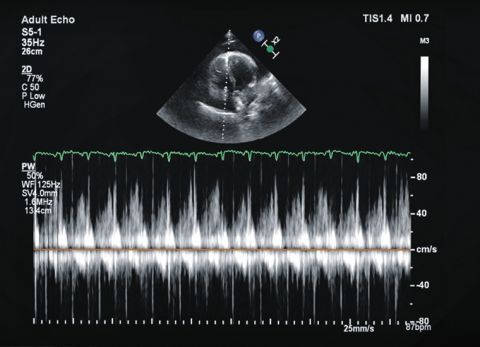

Wideo Echokardiografia. Przypadek 2

prof. dr hab. n. med. Piotr LipiecPacjent z ostrą dusznością i hipotonią, bez wcześniejszego wywiadu chorób układu krążenia.